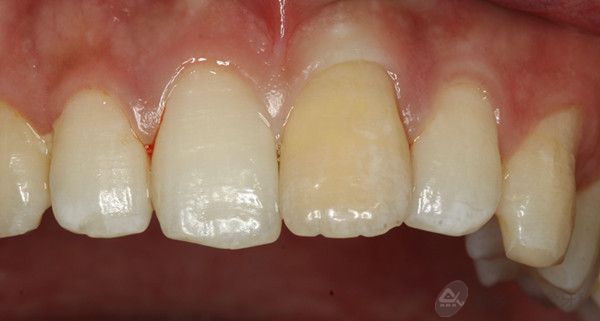

4.jpg

治疗中